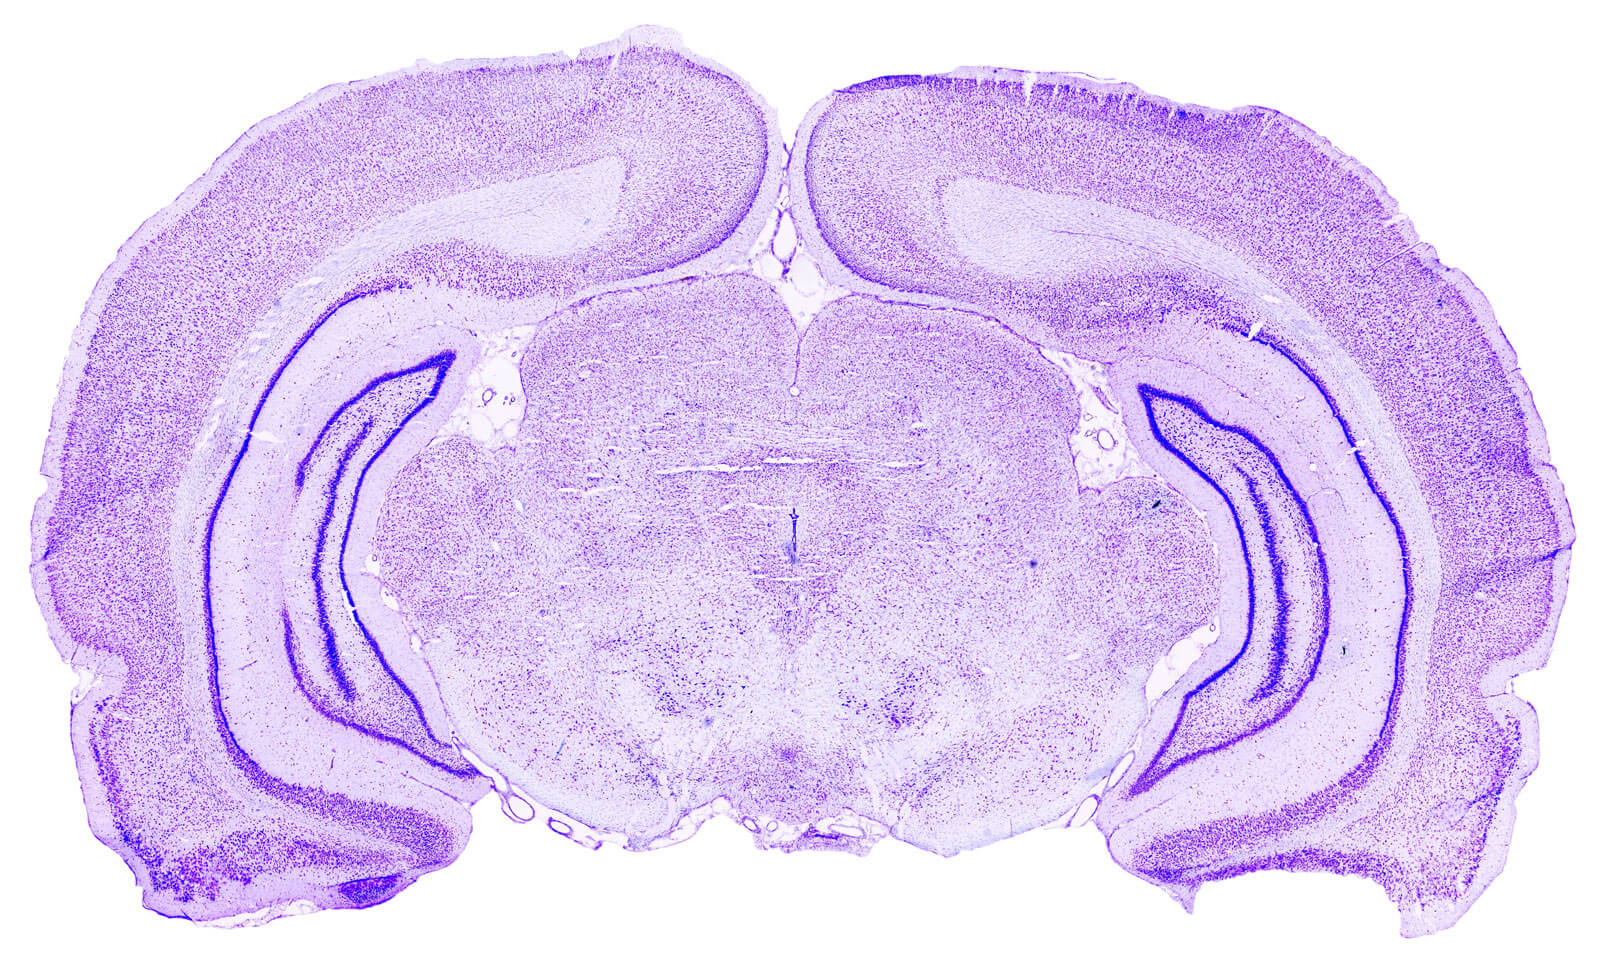

Immunohistochemistry, Immunofluorescence, and Histology

BRAINXPLORE conducts preclinical pharmacology studies dedicated to Central Nervous System (CNS) disorders on your behalf, combining CRO‑level industrial standards with the scientific expertise of a research laboratory. We offer a complete range of services from cell to animal: lead optimization, POC, Neuro-PK, PK/PD, biomarker discovery, to meet your specific needs. We have three areas of expertise in Neurology: neurodegenerative diseases (Alzheimer’s, Parkinson’s), psychopharmacology (Anxiety, Depression, Cognition), and Stroke. All our models are customizable.